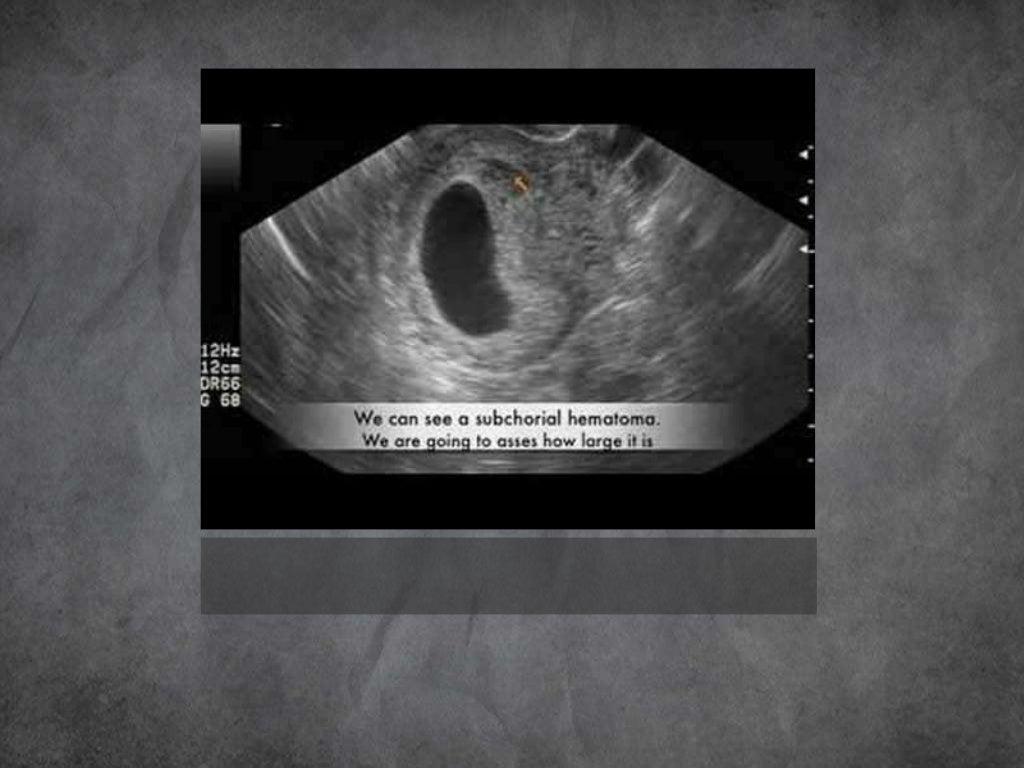

Imaging In Obstetrics First, Mid And Third trimester Ultrasound

Imaging In Obstetrics First, Mid And Third trimester Ultrasound Diagnostic Imaging Obstetrics Woodward Obstetrics, fourth edition, is an invaluable. Featuring approximately 260 diagnoses highlighting the most recent information, references, and images, this title serves as a. The newest edition of diagnostic imaging: The newest edition of diagnostic imaging: The newest edition of diagnostic imaging: Diagnostic Imaging Obstetrics Woodward.